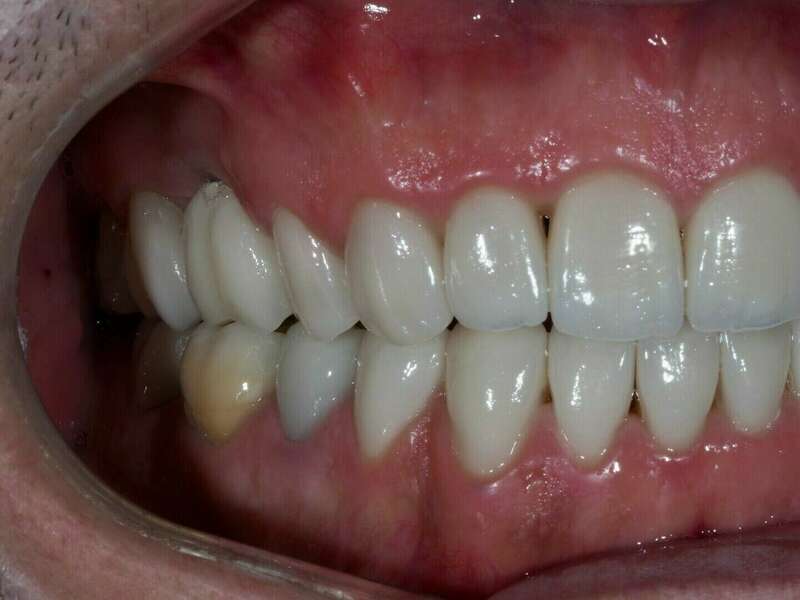

- Réalisation des couronnes ,facettes et de 3 couronnes sur implant en céramique Emax stratifiée

Après